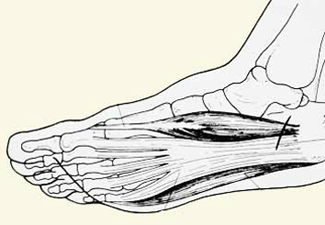

La fascia plantar es una banda fibrosa que se extiende desde su origen, en el talón, hasta la base de los dedos, como si fuera una cuerda de arco. Es plana en el perfil, pero tiene forma de abanico si la observamos desde la planta del pie. Esta estructura se encuentra cerca de su origen en relación muy cercana con estructuras vasculares y nerviosas que pueden ser comprometidas cuando la misma presenta un cuadro inflamatorio. Por eso mismo es importante descartar otras patologías que habitualmente presentan una sintomatología similar, y son de tratamiento completamente diferente.

Esquema anatómico de la fascitis plantar.